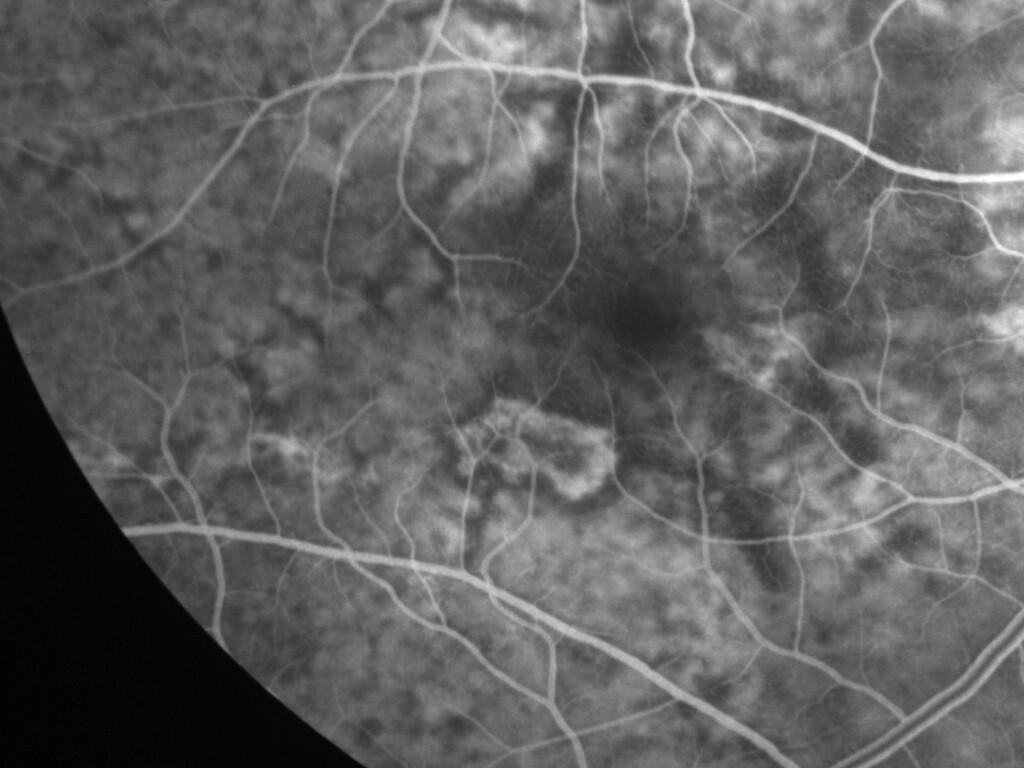

ASSOCIATION STRIES ANGIOIDES ET DYSROPHIE MACULAIRE RETICULEE

NEOVASCULARISATION